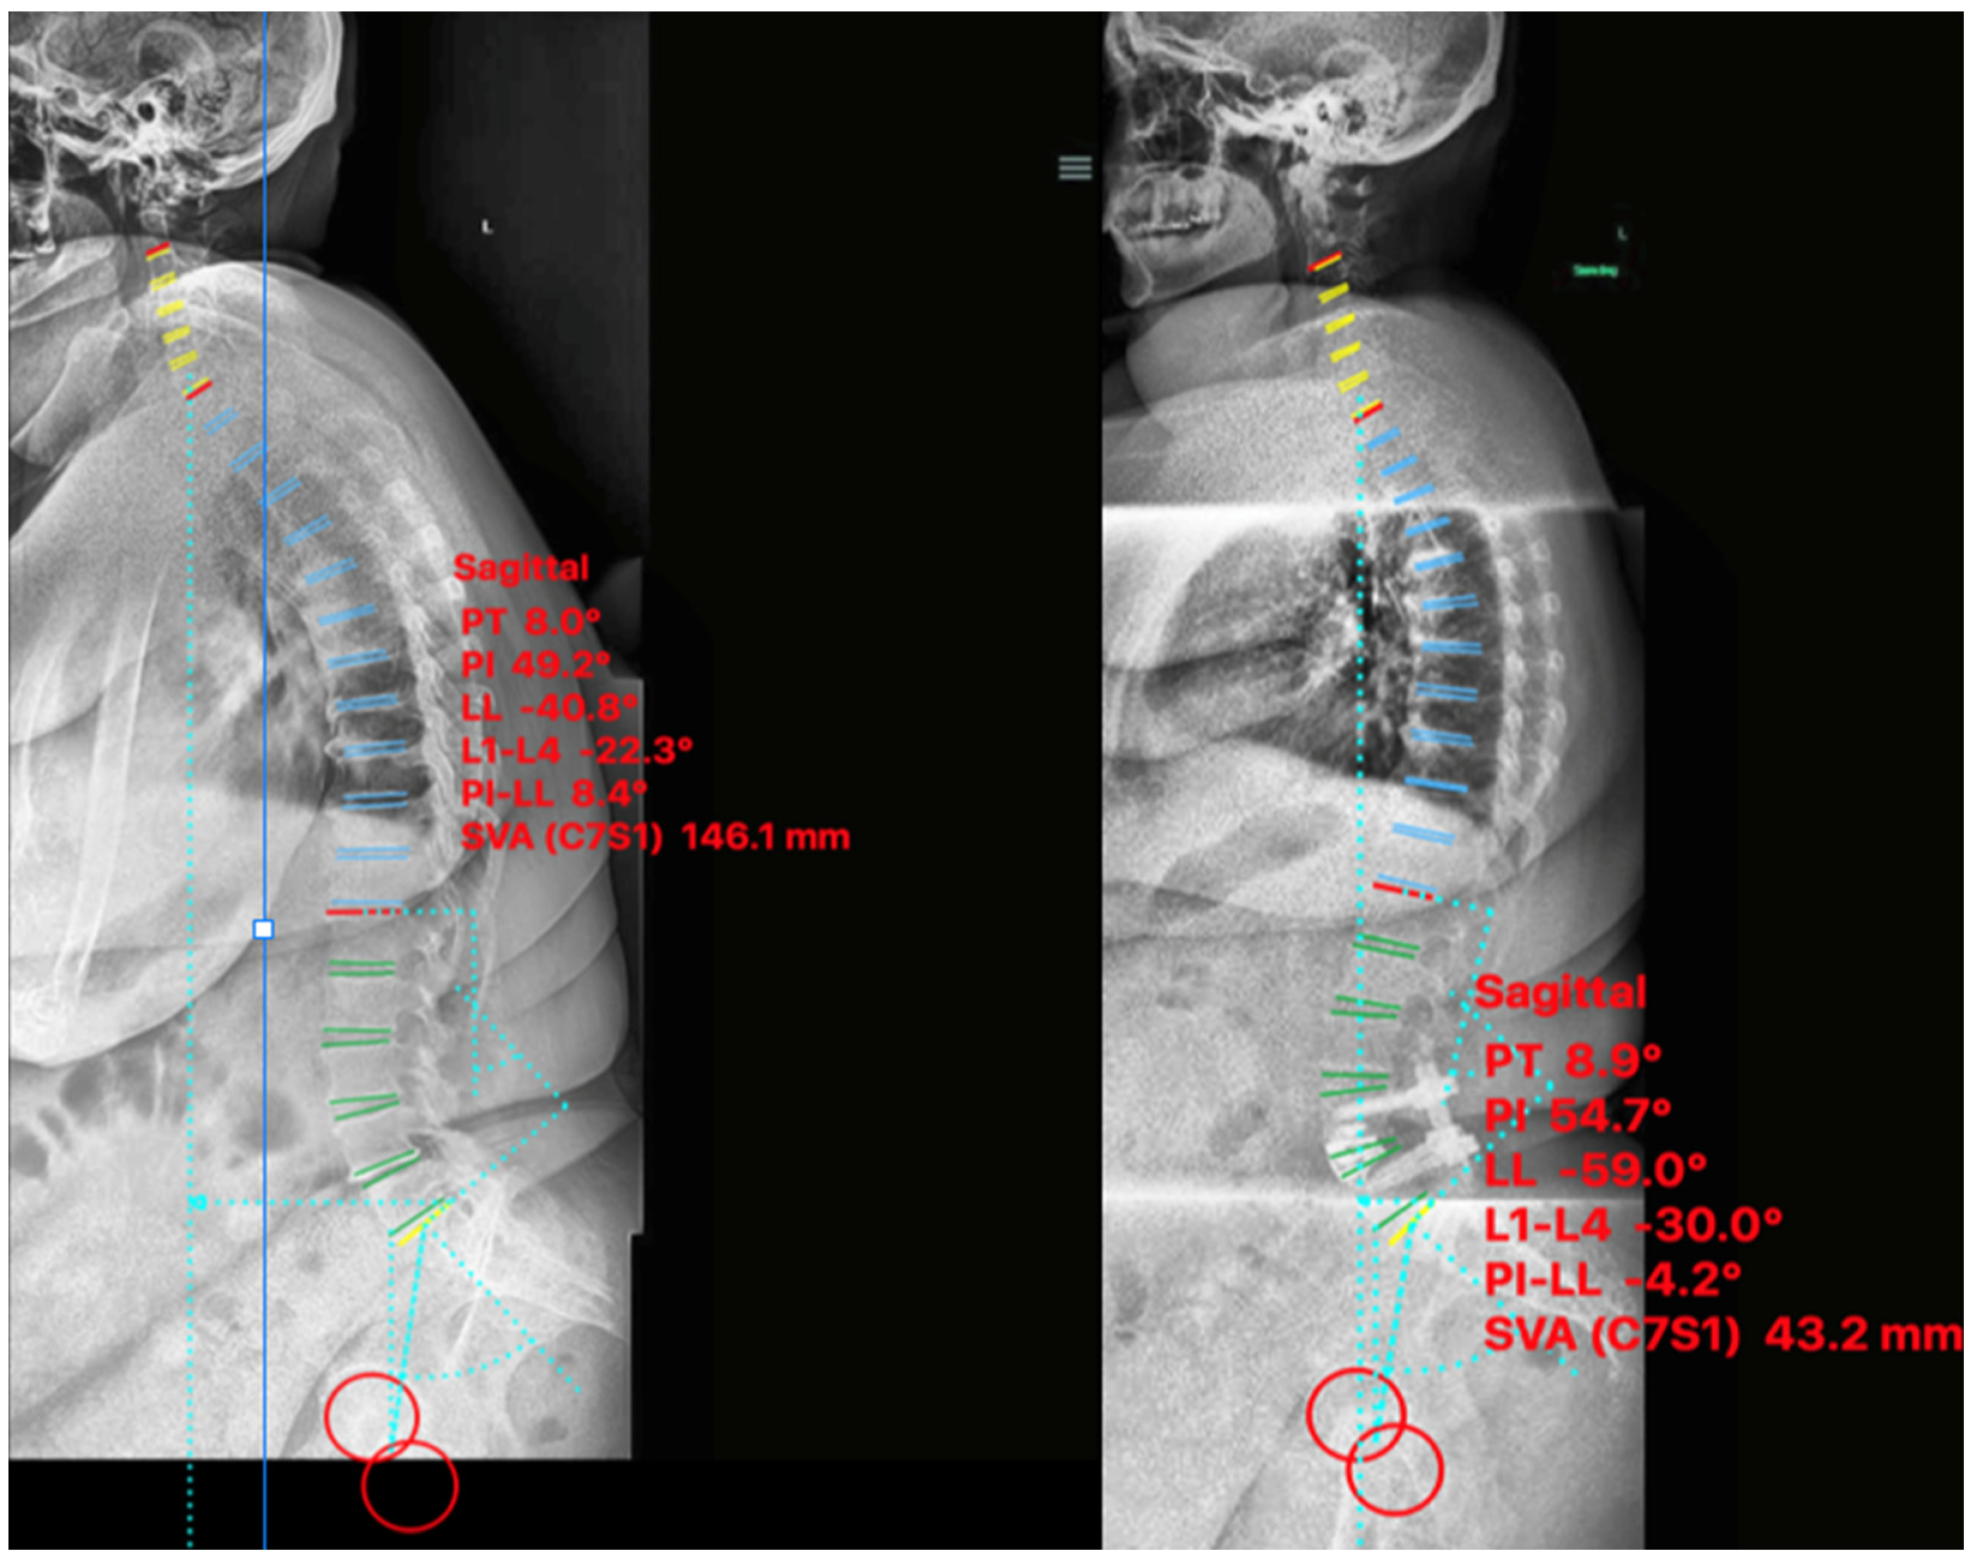

2.4.2. Case II

2.4.3. Case III